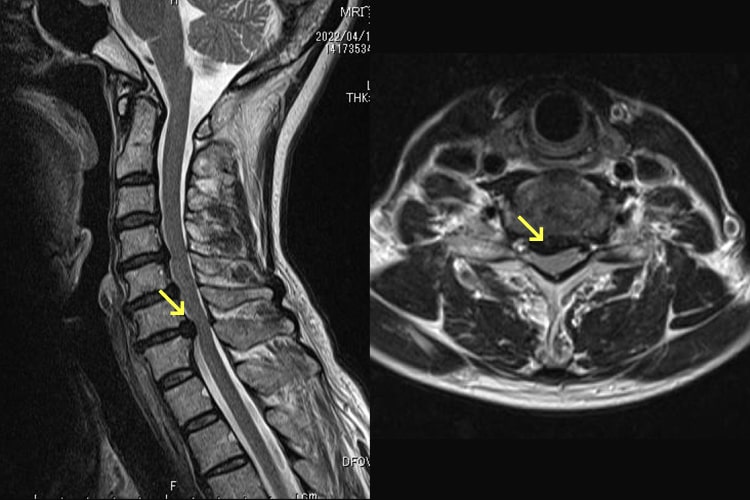

頚椎症性脊髄症

ボタンのかけ外し、お箸の使用、書字が不器用になったり、歩行で脚がもつれるような感じや手足のしびれも出てきます。比較的若い方であれば、かけ足やケンケンをしにくくなるなどの軽度の症状を自覚できますが、高齢者では気づくのが遅れる場合があります。転倒などの軽微な外傷で四肢麻痺(脊髄損傷)になる危険性がありますので、転倒しないように注意します。一般的に日常生活に支障があるような手指巧緻運動障害や痙性歩行障害、神経因性膀胱などが見られるようになれば手術的治療が選択されます。